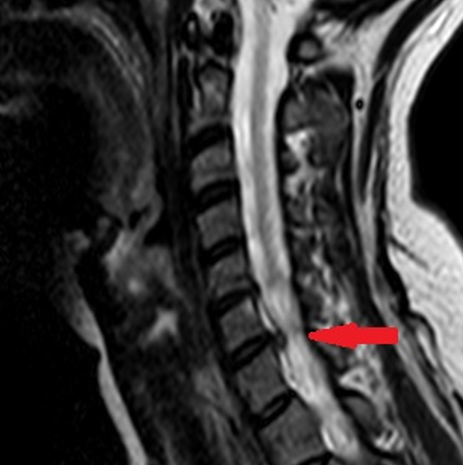

Cervical Spine Case

What is his diagnosis?

What does the MRI show?

• 68 yo male

• Active/healthy

• Was lifting weights (bench press) when he suddenly felt pain in his neck as well as shooting pain down his left arm to his middle finger

• Tried rest, heat, Advil

• After 2-weeks, while he feels a bit better, the neck pain and arm symptoms have continued and he makes an appointment to see you

• Physical:

• Inspection

• Normal gait, not broad-based

• Skin intact

• Palpation

• Moderate tenderness in region of lower cervical spine, no palpable step-off

• ROM

• Full flexion/extension/rotation (but feels stiff and somewhat painful)

• Sensation

• Intact except slight numbness to left middle finger

• Motor:

• 5/5 all throughout (which muscle group are you particularly interested in?)

• C7: Elbow extension / wrist flexion / MF extension

• Reflexes:

• Normal

A

C7 Radiculopathy

C7 Herniation